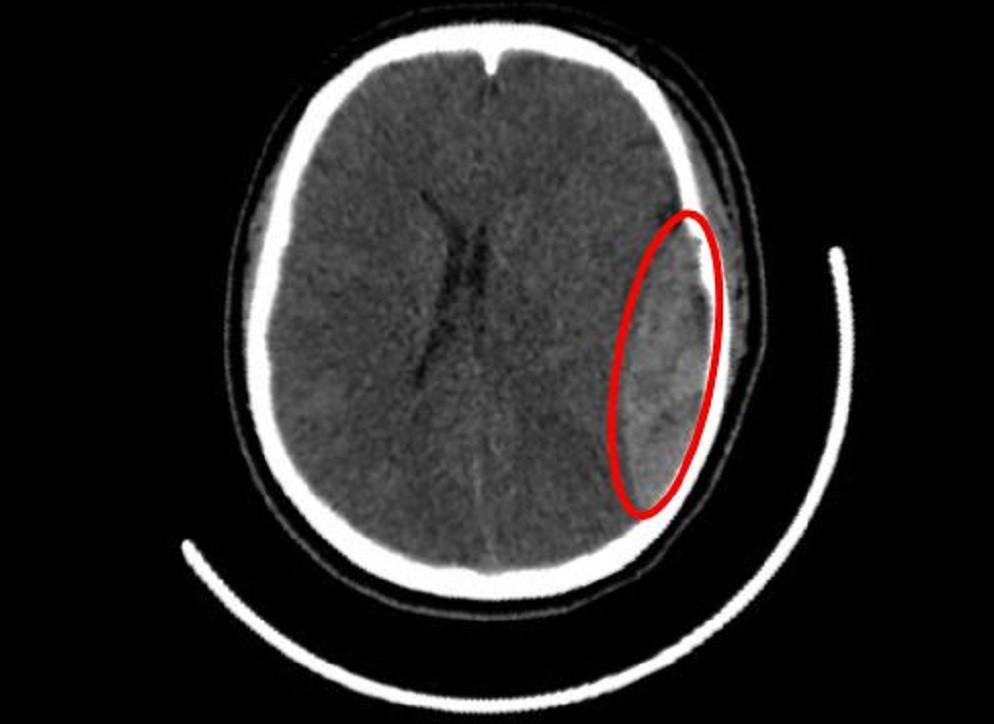

Kết quả chẩn đoán hình ảnh và mức độ tổn thương

Qua các xét nghiệm CT scan não bộ, bác sĩ phát hiện xuất hiện máu tụ ngoài màng cứng cùng với vết nứt hộp sọ tại vùng thái dương bên phải. Mức độ tổn thương không chỉ giới hạn ở phần xương mà còn ảnh hưởng trực tiếp đến mô não bên trong gây áp lực gia tăng. Kết quả chẩn đoán giúp ekip y bác sĩ lập kế hoạch phẫu thuật khẩn cấp nhằm giải tỏa áp lực vùng tổn thương.